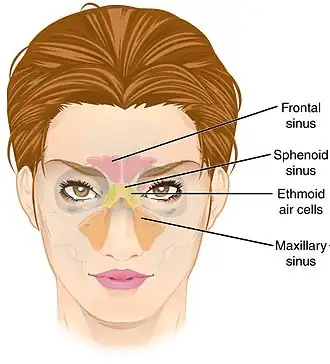

Paranasal sinuses seen in a frontal view | |

Paranasal sinuses are a group of four paired air-filled spaces that surround the nasal cavity.[1] The maxillary sinuses are located under the eyes; the frontal sinuses are above the eyes; the ethmoidal sinuses are between the eyes, and the sphenoidal sinuses are behind the eyes. The sinuses are named for the facial bones and sphenoid bone in which they are located. The role of the sinuses is still debated.

Humans possess four pairs of paranasal sinuses, divided into subgroups that are named according to the bones within which the sinuses lie. They are all innervated by branches of the trigeminal nerve (CN V).

- The maxillary sinuses, the largest of the paranasal sinuses, are under the eyes, in the maxillary bones (open in the back of the semilunar hiatus of the nose). They are innervated by the maxillary nerve (CN V2).[2]

- The frontal sinuses, superior to the eyes, in the frontal bone, which forms the hard part of the forehead. They are innervated by the ophthalmic nerve (CN V1).[2]

- The ethmoidal sinuses, which are formed from several discrete air cells within the ethmoid bone between the nose and the eyes. They are innervated by the ethmoidal nerves, which branch from the nasociliary nerve of the ophthalmic nerve (CN V1).

- The sphenoidal sinuses, in the sphenoid bone. They are innervated by the ophthalmic and maxillary nerve (CN V1 and V2).[2]